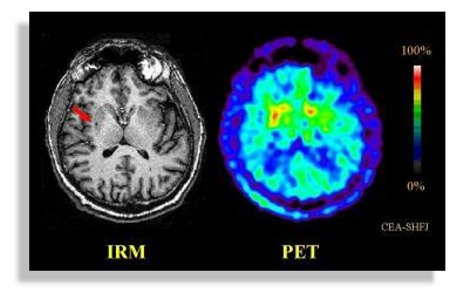

L’activité cérébrale, comme l’ont illustré les IRM, est un feux d’artifice permanent, elle est provoquée par d‘infimes décharges électriques qui parcourent notre cerveau à la vitesse de la lumière ; différentes zones du cortex s’activent, s’animent et s’illuminent ; elles correspondent entre elles et forment des nuages de pensée, coordonnent nos actions, reçoivent des émotions et des sensations… Pouvons nous devenir des êtres plus subtils et éviter la fascination mortifère pour un Super Ordinateur Central (Hall dans 2001 l’Odyssée de l’espace de Stanley Kubrick en 1968) qui viderai nos batteries d’énergies vitales jusqu’à la dernière goutte (Dark Cristal de Jim Henson et Frank Oz en 1982, Matrix par les frères Andy et Larry Wachowski en 1999) nous transformant en ectoplasmes cybernétiques ?…